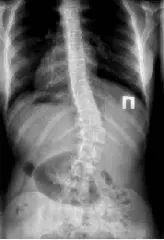

Рентген грудного відділу робитися в 2-ух проекціях (в прямій та боковій), в положенні лежачи. А, в разі викривлення, для оцінки різниці в відхиленні хребетного стовпа, робляться знімки в одній проекції, стоячи і так само лежачи – це дає можливість судити про стабільність або нестабільність хребта.

При діагностуванні ступеня сколіозу призначається функціональна рентгенографія грудного відділу. Для цього робиться два знімки в прямій проекції:

- Стоячи – пацієнт стає спиною до приймача рентген-апарату, промінь центрируется на середню область грудей, робиться знімок.

- Лежачи – робиться так само, як і звичайний знімок в прямій проекції.